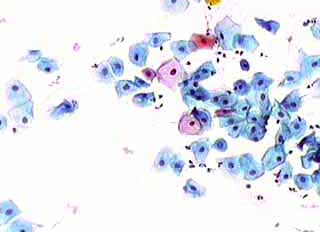

Η κυτταρολογικές εικόνες του έρπητα του τραχήλου της μήτρας, παρουσιάζουν πάντοτε ενδιαφέρον, επειδή οι αλλοιώσεις που προκαλεί είναι πολλαπλές και μπορεί να προβληματίσουν τον εξεταστή.

Ασυμπτωματική σθενής 23 ετών. Κολποσκοπικως κφ. Δοκιμασίες οξικου οξέως και lugol αρνητικές. Ακολουθούν εικόνες του έτους 2000: Kύτταρα κυρίως της επιφ. καi διαμέσου στιβάδος, κάπως μικρότερα απ' ότι συνηθως, με αρραιοχρωματικους φυσαλιδοειδείς πυρήνες . Πολλά απο αυτά με διακριτική κοιλοκυττάρωση και εκφυλυστικές αλλοιώσεις του πυρήνα. Επίσης αρκετά γιγαντιοκύτταρα και εκφυλιστικές αλλοιώσεις πυρήνων με διάλυση και εν μέρει ομοιογενοποίηση της χρωματίνης, που δίνουν την εικόνα θολού γιαλιού. (Mattglasphaenomen). Aρραιή βακτ. χλωριδα. Λιγα πολυμορφοπύρηνα. Aρνητικό για κακοήθεια. Aλλοιώσεις που συνηγορούν για HSV.

Οι αλλοιώσεις συνέχισαν να υπάρχουν 3 και 6 μήνες αργότερα. Μετά επί 18 μήνες και μέχρι σήμερα (Οκτ. 2002), τα επιχρίσματα που πήραμε ανα 6μηνο, ήταν τελείως φυσιολογικά.